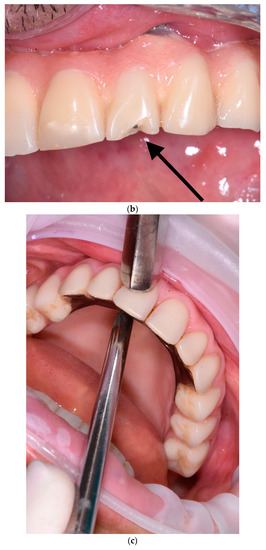

The second step consists of the examination of the soft tissues next to the implants and the prosthesis. In this phase, transmucosal decubitus (Figure 4a), fenestrations, hypertrophy (Figure 4b), fistulas (Figure 4c), and dehiscence (Figure 4d) must be identified and registered. In these cases, the prosthesis is unscrewed to assess peri-implant tissues and the morphology of the prosthodontic framework; investigations are conducted regarding any difficulties in maintaining hygiene due to inadequate space between the gums and the prosthesis. The devices to be used in this phase are retractors (i.e., Optragate, Ivoclar Vivadent, Schaan, Liechtenstein), gauze, and optical magnifiers.

Figure 4.

(a–d) Intraoral pictures of possible biological complications of zygomatic implants: decubitus (a), hypertrophy (b), fistulas (c), and dehiscence (d).